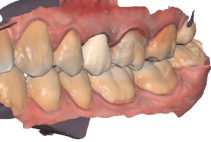

COROAS E FACETAS DE PORCELANA UNITÁRIAS

As coroas ou lentes de porcelana também tem ampla indicação em casos unitários : dentes fraturados, escurecidos após tratamentos de canal, alterações de forma e manchas que não respondem ao clareamento, são exemplos de situações em que precisamos harmonizar esse novo dente com os vizinhos.

Espelhar um dente vizinho com uma nova coroa ou faceta de porcelana, é um procedimento altamente técnico, que requer a habilidade e experiência de um dentista estético e de um laboratório qualificado.